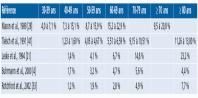

- eTableau 13-1 - Prévalence du GPAO dans les études épidémiologiques réalisant un dépistage... :

- eTableau 13-2 - Prévalence du GPAO en fonction de la classe d’âge dans des populations composées partiellement ou complètement de sujets mélanodermes :